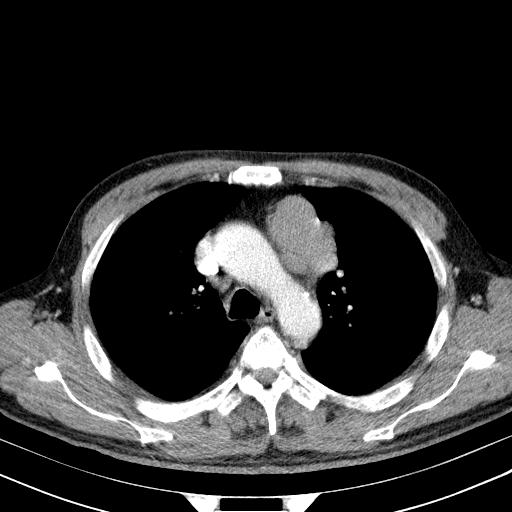

经典?纵膈多发肿大淋巴结。腹膜后未见异常。

1)考虑淋巴瘤。2)双侧少量胸腔积液。

多发肿大淋巴结影,肝内改变需结合强化观察